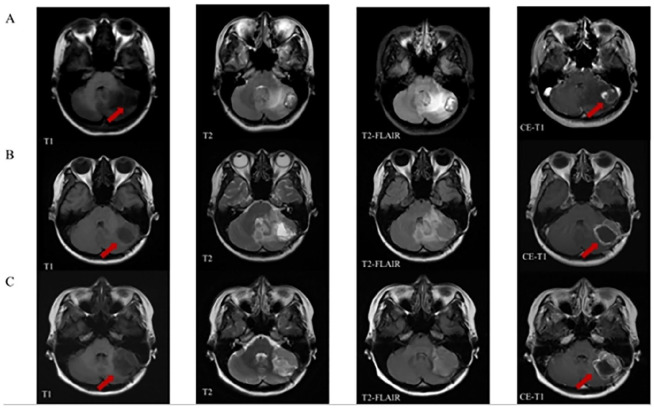

Case presentation: Here, we present a case of a middle-aged female with lung cancer BM, whose condition was assessed as progressive post-standard treatment including two local surgeries (both involving resection of cerebellar space-occupying lesions), stereotactic radiotherapy, chemotherapy and EGFR-TKIs. Subsequently, she underwent treatment with the traditional Chinese herbal formula gubenxiaoyi (GBXY). The patient was treated with GBXY for a total duration of 55 months. After treatment, a significant reduction of about 50% in intracranial lesions was observed, accompanied by an extension of both Intracranial Progression-Free Survival (IPFS) and Cognitive Deterioration-Free Survival (CDFS) exceeding 50 months.

Conclusion: These results demonstrate that in patients with lung cancer brain metastases (BM) unresponsive to standard treatments, GBXY not only has the potential to effectively prolong IPFS and decelerate cognitive decline, but may also contribute to a reduction in intracranial tumor burden. This suggests that GBXY could be a promising therapeutic option that warrants further investigation.